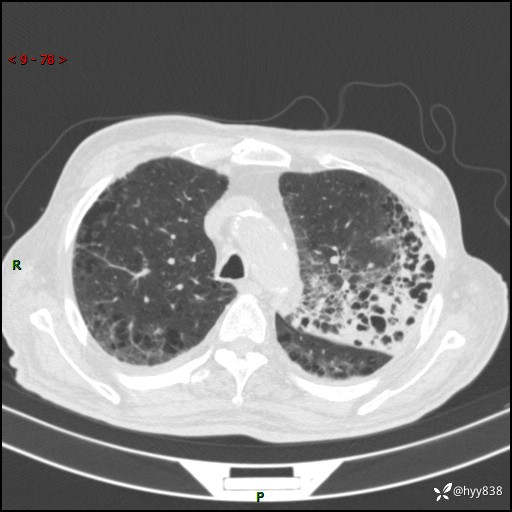

老年男性,间断咳嗽咳痰20余年,加重伴发热1天。呼吸科疑难病例讨论---结果公布

主诉:间断咳嗽咳痰20余年,加重伴发热1天

简要病史:家属代诉患者于20余年前无明显诱因出现咳嗽咳痰,痰为白色泡沫状,未行特殊治疗,不伴胸痛、胸闷、气喘、咳血等不适,1天前上午患者无明显出现发热,查体温39℃,伴咳嗽,咳痰无力,自行予以物理降温对症治疗,今晨2点左右再次出现发热,体温达40℃,自行服用复方氨酚烷胺对症治疗,凌晨3点左右复测体温38.2℃,现患者为求进一步诊治于今日就诊于我院门诊,行胸部CT提示双肺感染,遂以“肺部感染”收入我科。 患者本次起病来精神、食欲、睡眠欠佳,体力下降,体重无明显变化。

辅助检查:CT

胸部CT平扫